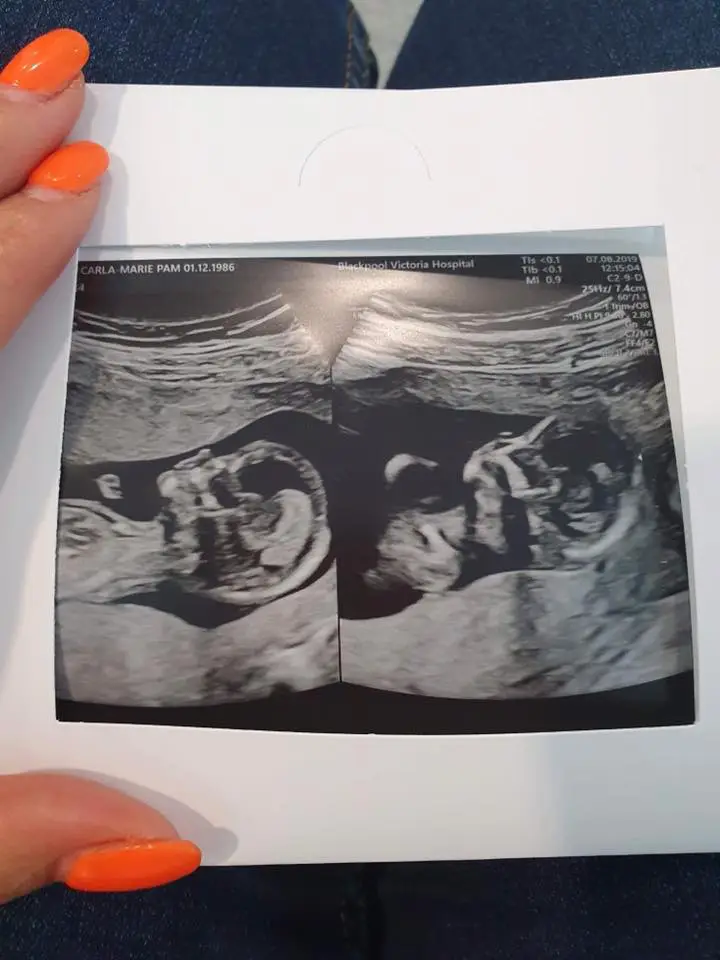

I was 15 weeks 4 days pregnant and carrying rare twins. My twins were identical, in the same sac and sharing the same placenta also known as “Monochorionic-monoamniotic twins” . I knew there was a risk attached with these types of twins, but I also had risks with my son George 4 and although I had a traumatic birth he was ok. We had to have scans every two weeks and as we were jetting off on our baby moon in Portugal my midwife was insistent we had a scan before we went.

The pregnancy was going smoothly, I did have the odd bleed but upon checking the twins they could never identify the problem I was 15 weeks 4 days and I was at my regular fortnightly scan. I was told we could potentially find out the sex during this scan and I was convinced I didn’t want to know.